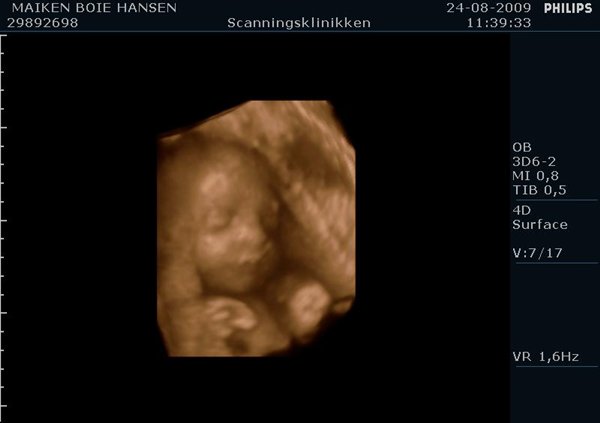

Jeg har lige været til en 3D/4D scanning (27+0), hvilket var en kæmpe oplevelse. Jeg venter en dreng på foreløbig 976 gram

Denne tråd er for alle os som har fået foretaget sådan en scanning. Jeg tænkte det kunne være sjovt at smide nogle fotos op af vores bebzere, da de lå i maven. I profil og forfra.

Skriv gerne hvilken uge scanningen er foretaget, samt evt. hvad køn det er